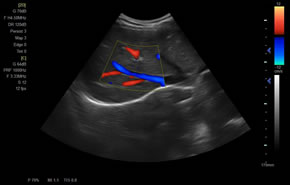

> 彩色血流量圖(CDE)

廣泛適用于腹部、婦產(chǎn)科、心臟、小器官、乳腺、肌骨及外周血管等諸多方面的診查,讓您在臨床超聲診斷應用領域得心應手,綻放異彩。